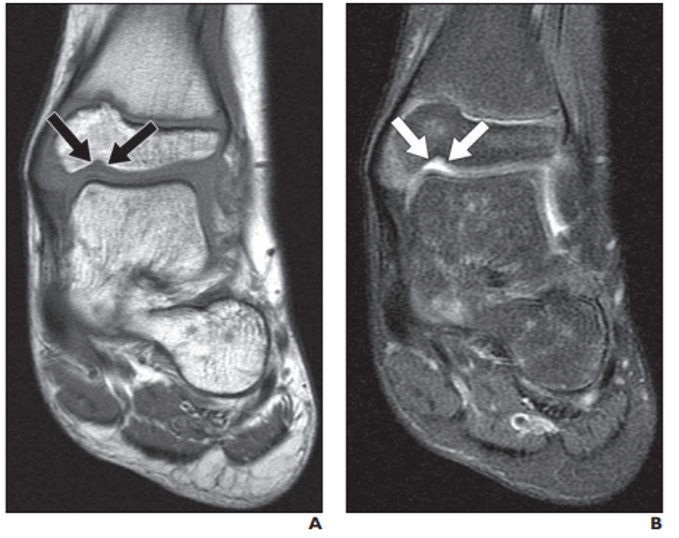

Meniscal ossicle

normal variant - don’t confuse this with a fracture!!

may be associated with meniscal root tears